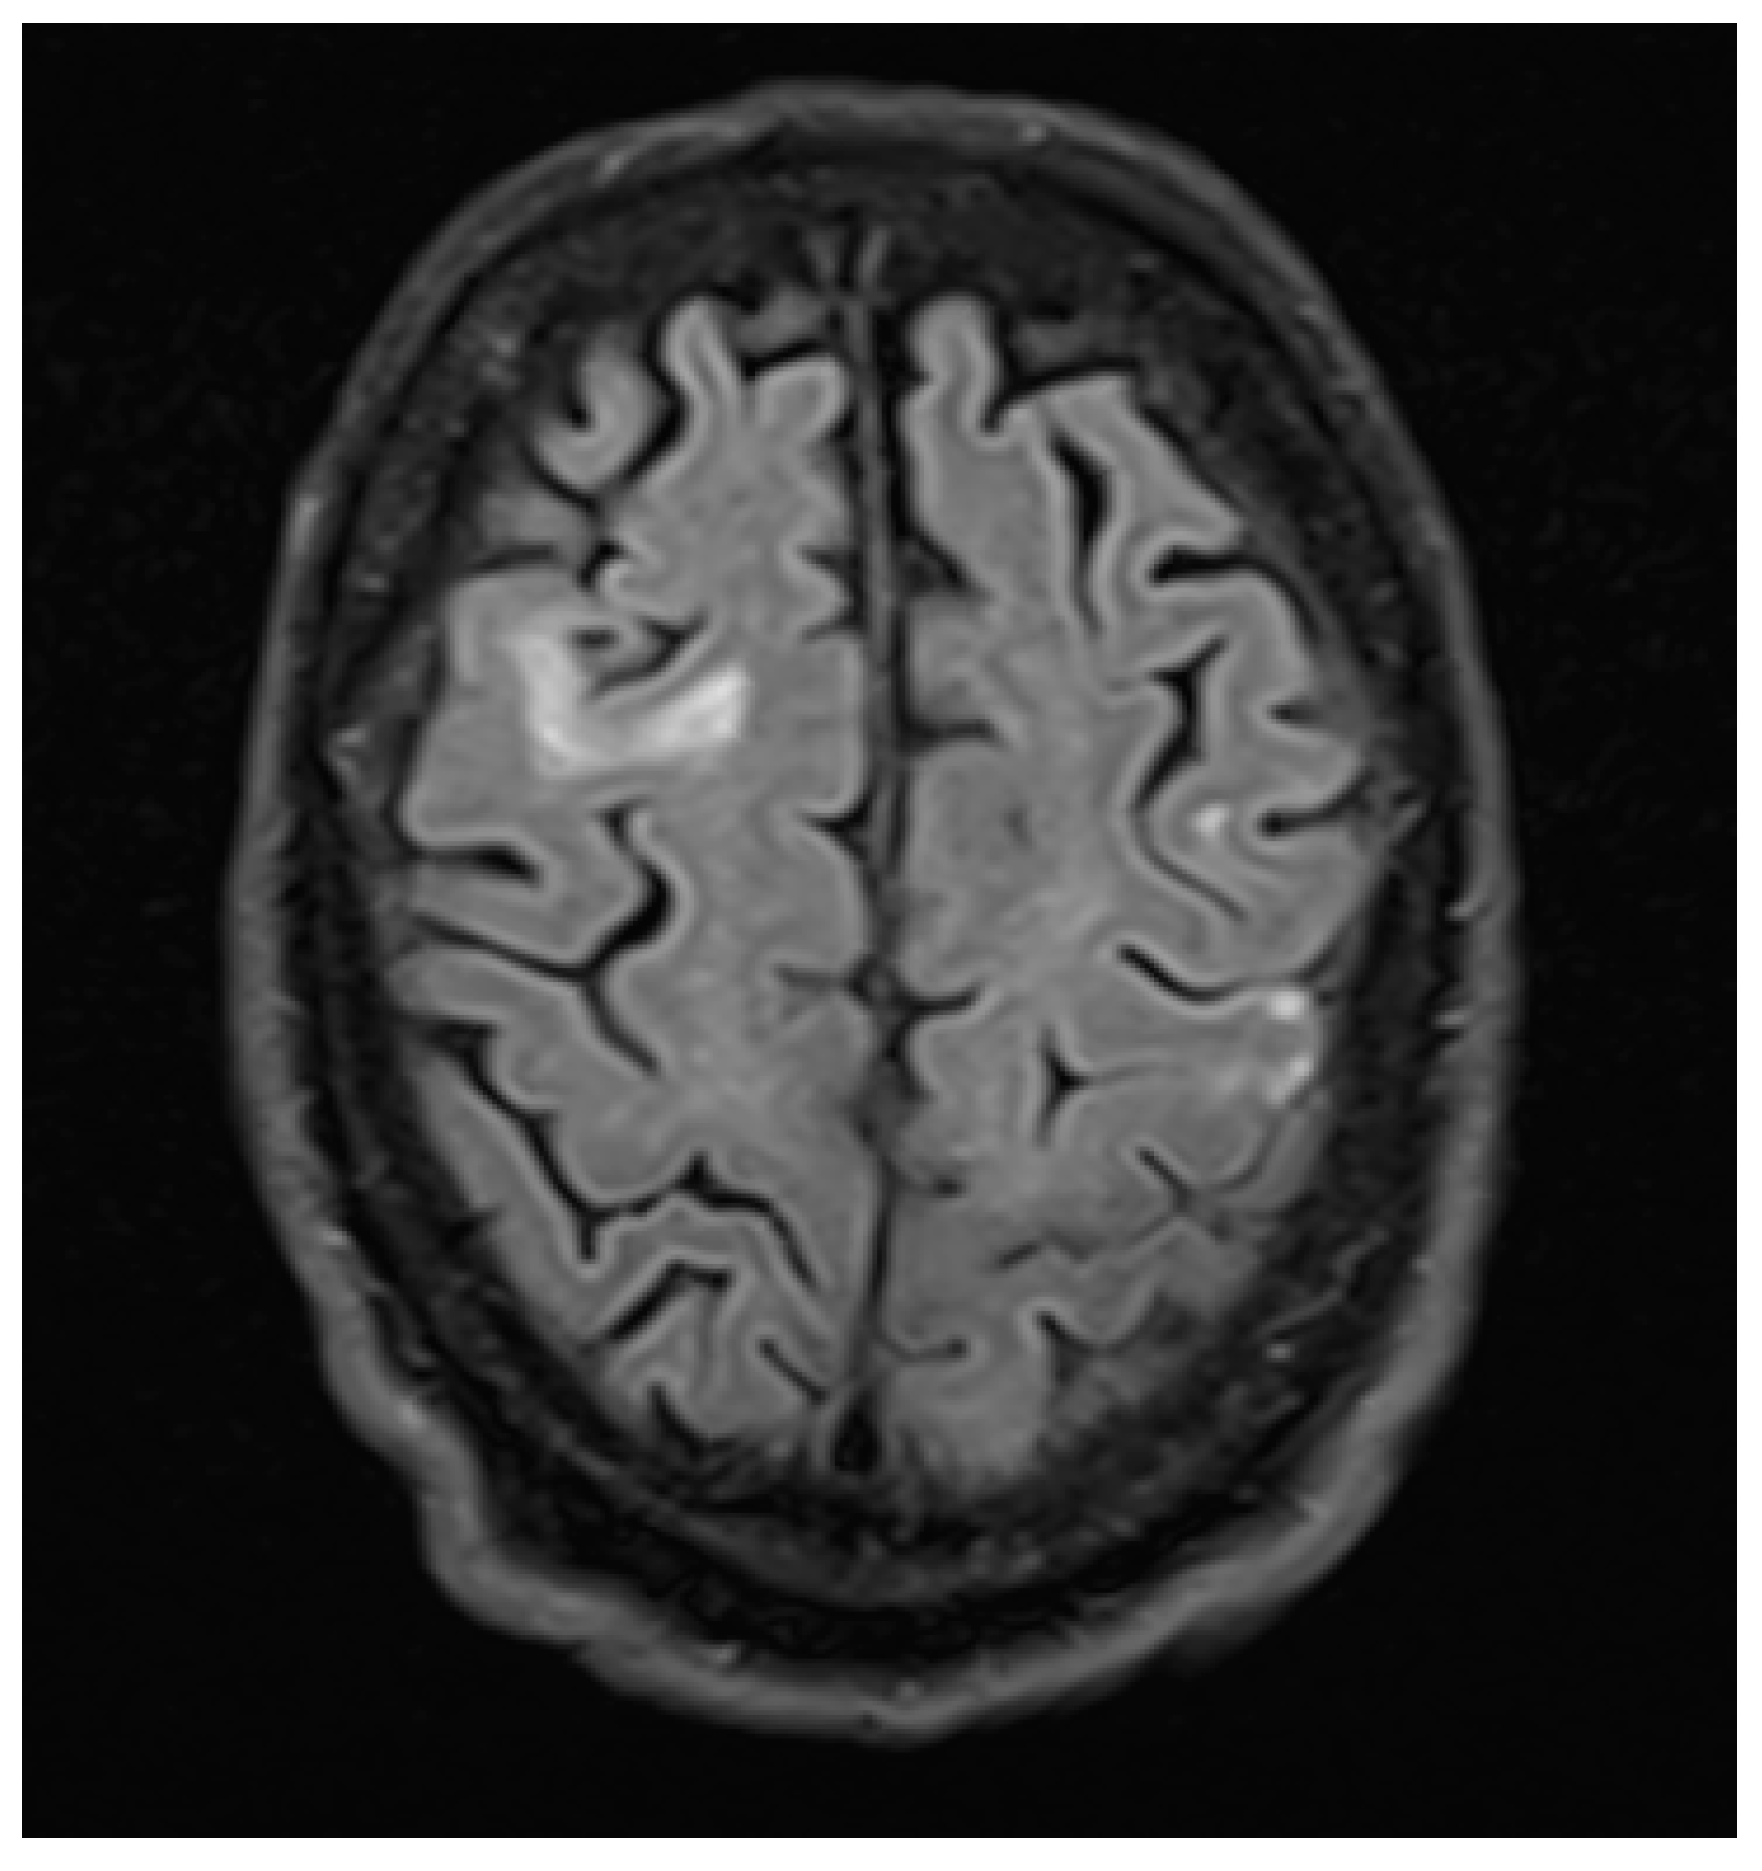

3. Case Report